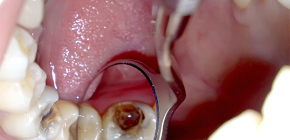

La rimozione di un nervo da un dente è una procedura molto importante, che, purtroppo, non sempre va bene per il paziente. Una preparazione impropria per il lavoro con il "nervo" e gli errori medici possono portare a conseguenze terribili, dal terribile dolore durante e dopo l'estrazione della polpa, al sanguinamento dal dente e uno strumento rotto e dimenticato nel canale. Perché è generalmente necessario rimuovere il nervo dal dente, come ciò accade e quali problemi possono aspettarti lungo il percorso - ne parleremo più in dettaglio in modo più dettagliato ...